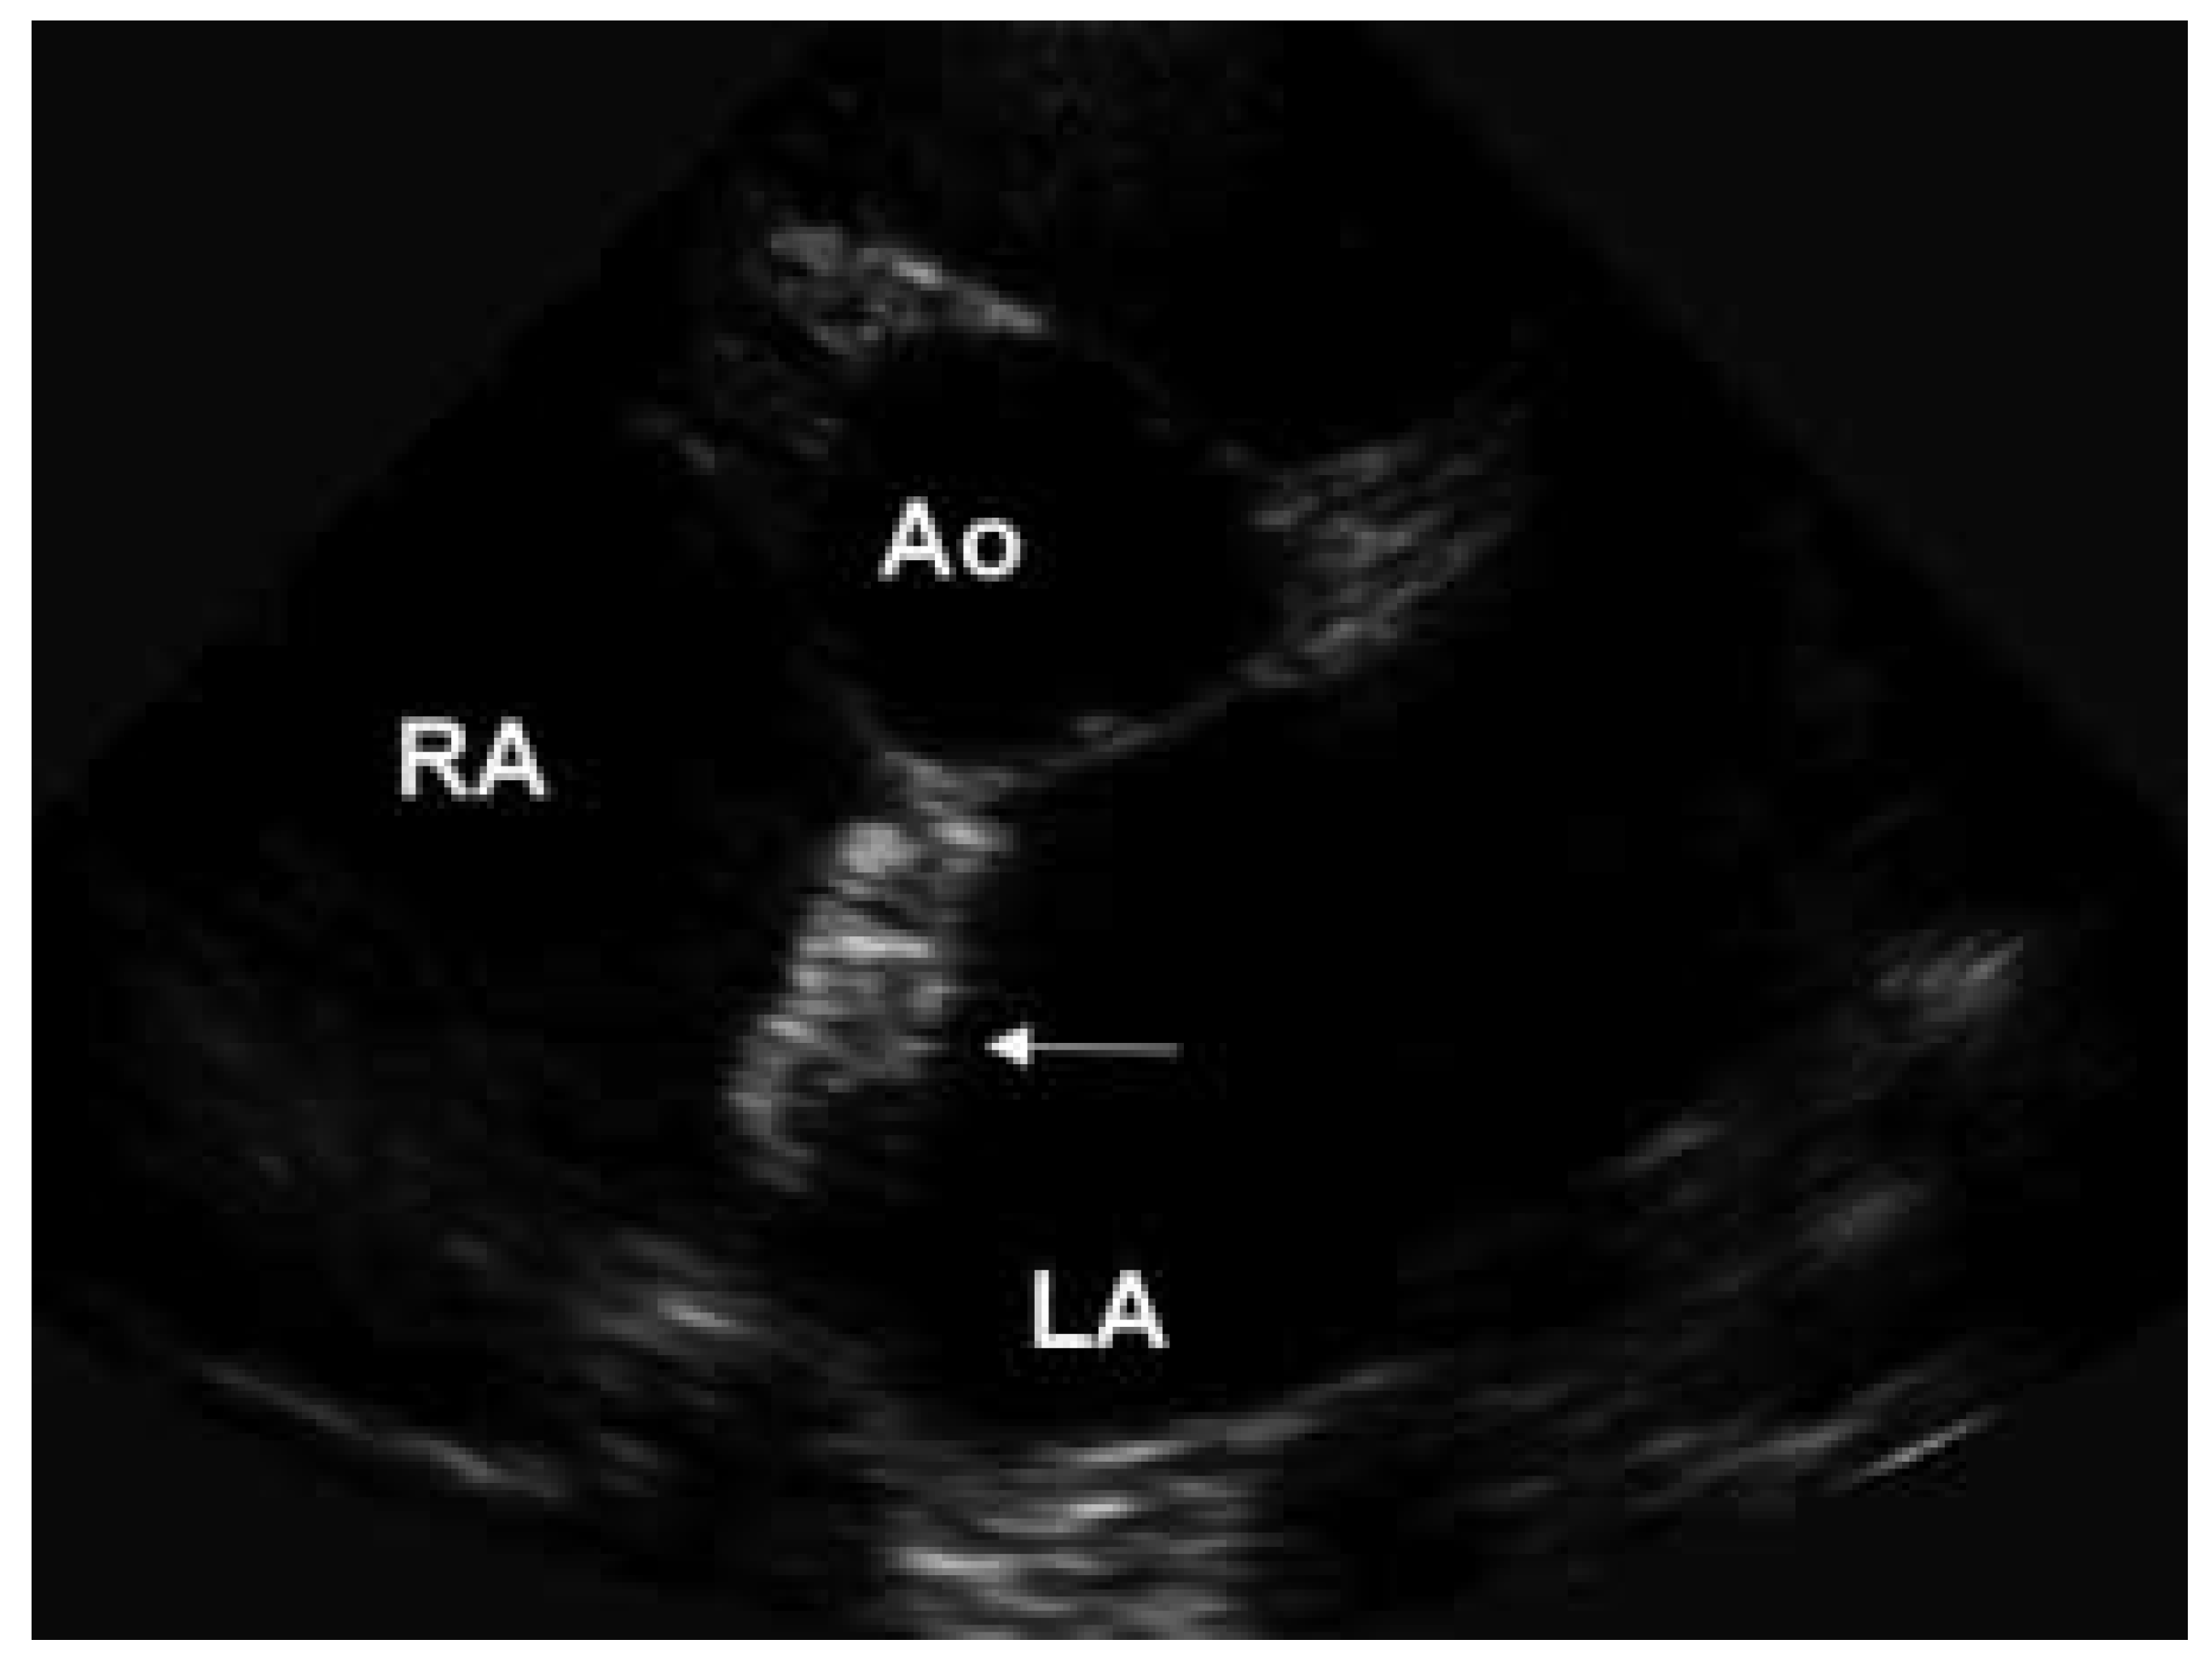

Heutzutage werden alle Arten von Piercing in allen möglichen Körperteilen gefunden. Wir berichten von einer 57jährigen Patientin, bei welcher im Alter von 17 Jahren ein operativer Verschluss eines grossen Vorhof-Septum-Defektes erfolgte. Wegen eines relevanten residuellen Links-Rechts-Shuntes erfolgte aktuell ein invasiver kathetertechnischer Verschluss mittels Amplatzer Okkluder. Die hier präsentierten Bilder wurden anlässlich einer transthorakalen echokardiographischen KontrollUntersuchung drei Monate nach Verschluss des Defektes aufgenommen. Auf dem parasternalen Kurzachsen-Schnitt konnte eine stabile, regelrechte Lage des Amplatzer Okkluder bestätigt werden (Abb. 1a). Ein residueller Links-Rechts-Shunt bestand keiner mehr. Interessanterweise konnte der Amplatzer Okkluder auch auf dem parasternalen Langachsen-Schnitt dargestellt werden, wo er sich wie ein spezielles «atriales Piercing» präsentierte (Abb. 1b). Die drei Ringe entsprechen bei schräger Ansicht den beiden linksund rechts-atrialen Schirmen sowie dem Verbindungsstück des Okkluders.

Abbildung 1a. Parasternaler Kurzachsen-Schnitt. Pfeil = Amplatzer Okkluder; Ao = Aorta; LA = linker Vorhof; RA = rechter Vorhof; LV = linker Ventrikel; RV = rechter Ventrikel.